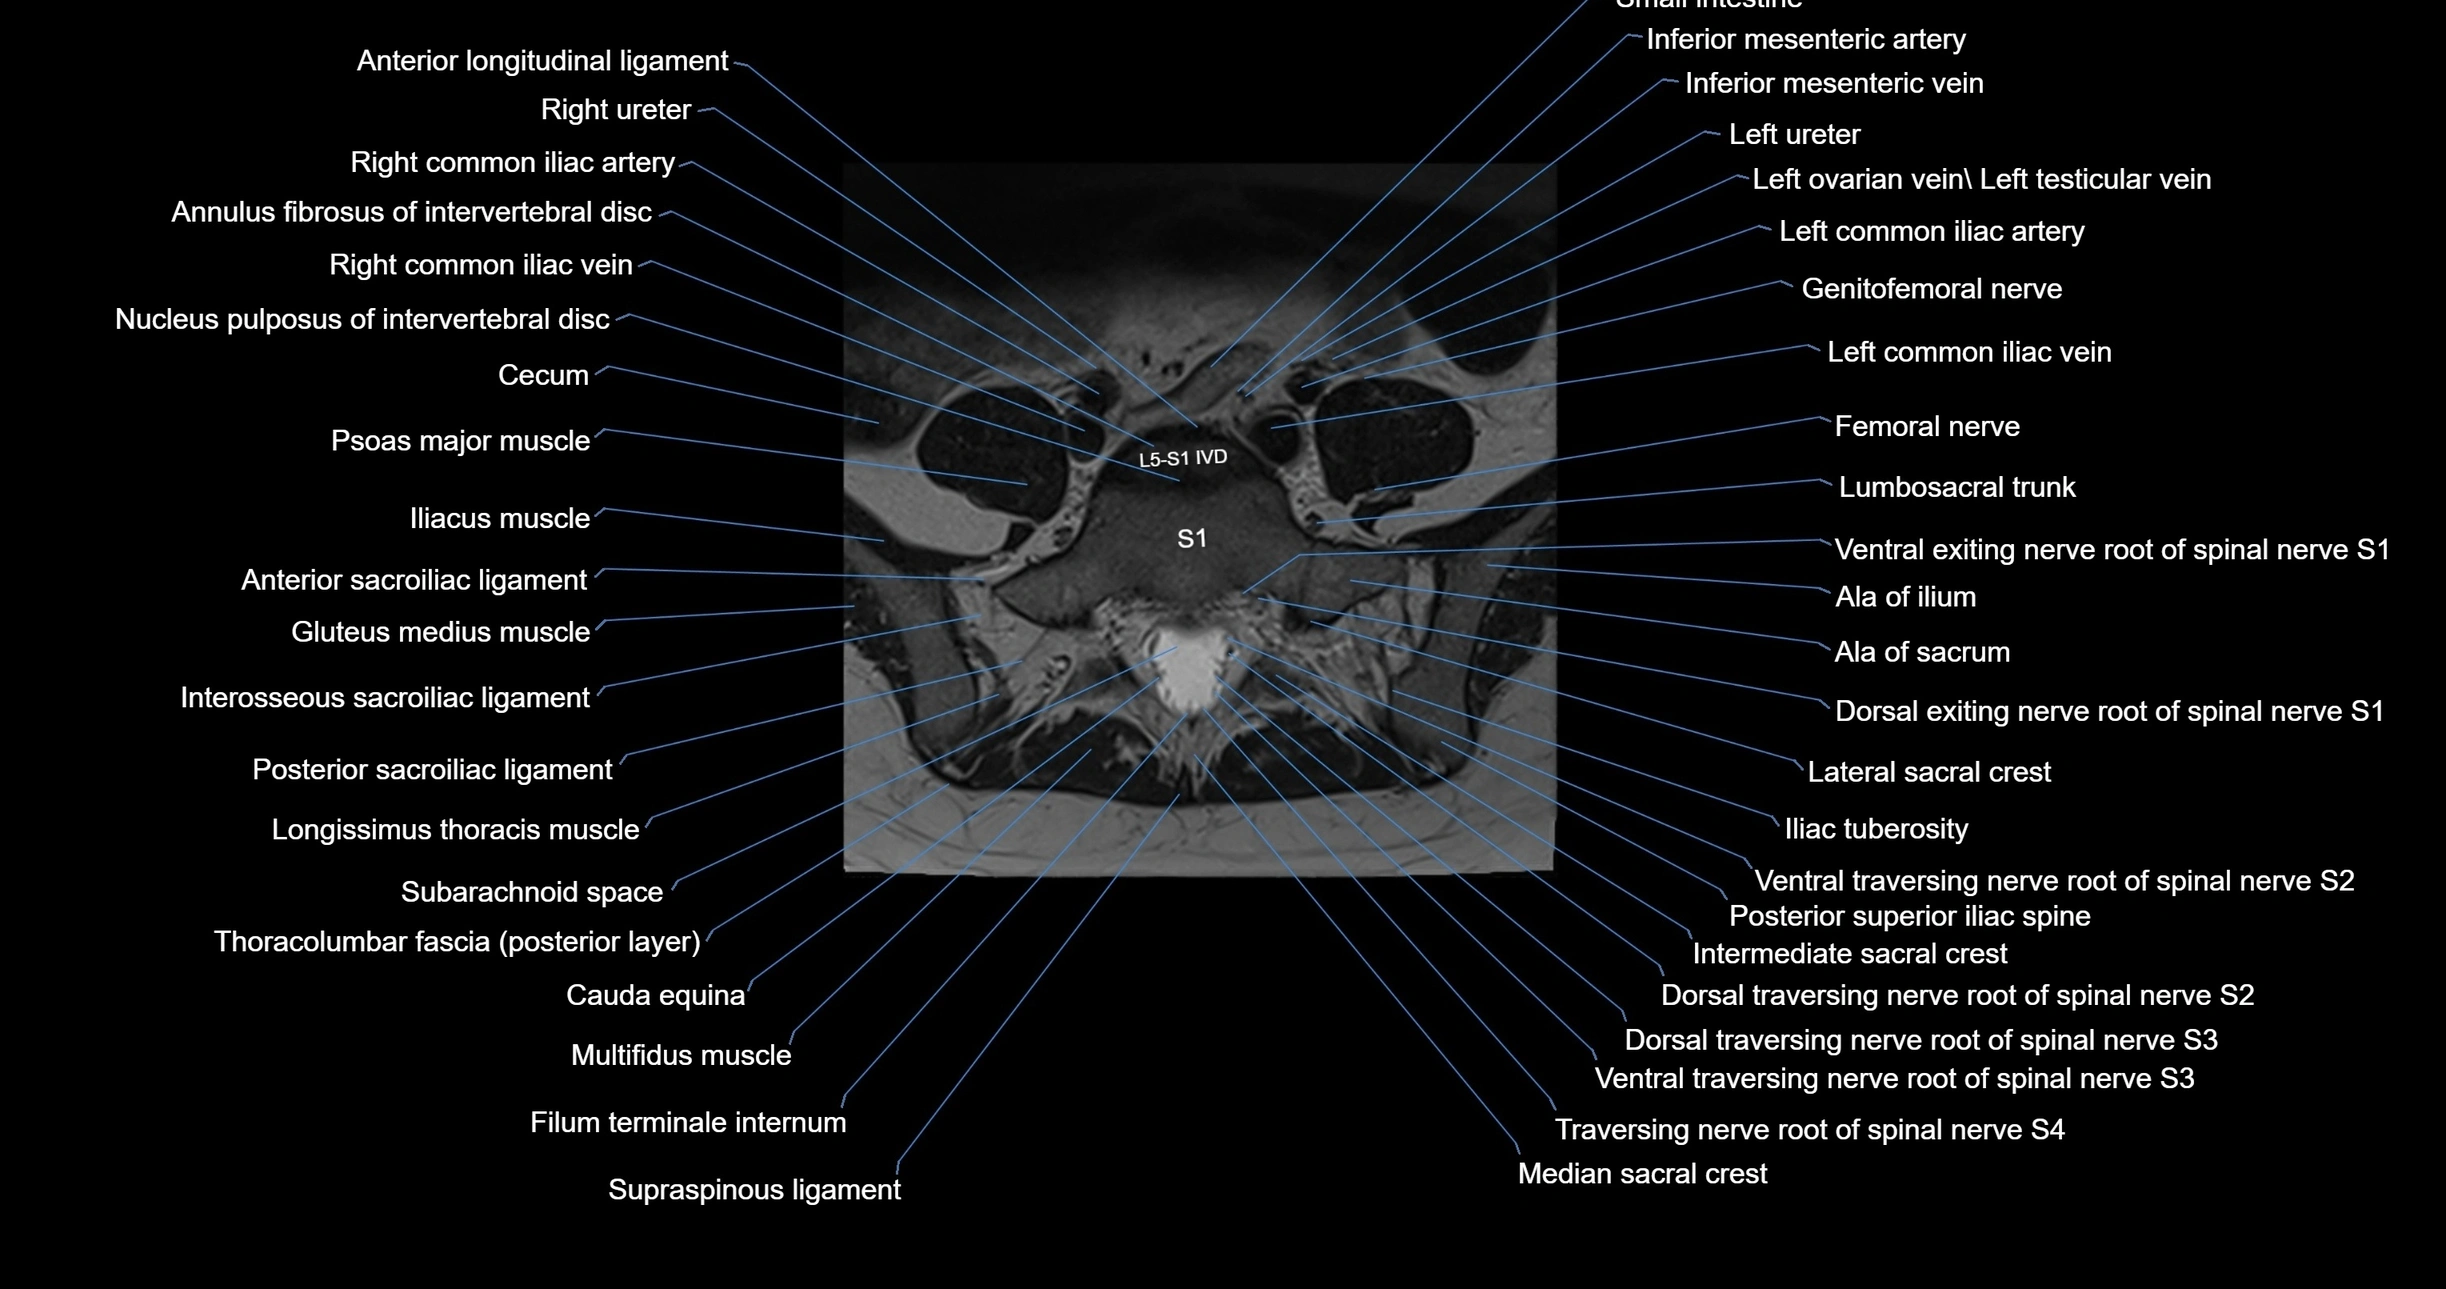

MRI images